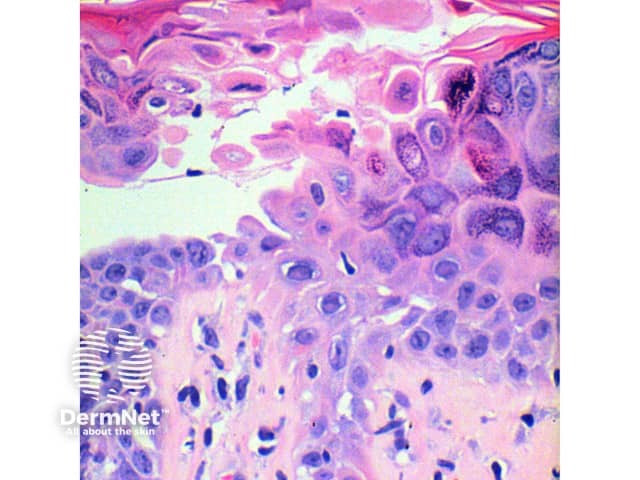

The scanning power view of the histology of Darier disease is of an epidermal and superficial dermal inflammatory process (Figure 1). Intraepidermal separation may be visible at this power, which on closer inspection is seen as suprabasal acantholysis (Figures 2 and 3). Acantholysis can be seen at all levels within the epidermis. Dyskeratosis of the keratinocytes is seen, with two notable changes described. Corps ronds refer to cells with small pyknotic nuclei, a perinuclear clear halo and eosinophilic cytoplasm (Figures 4 and 5).

Grains are compressed cells with elongated nuclei seen in the stratum corneum and granular layer (Figures 4 and 5).

Figure 3